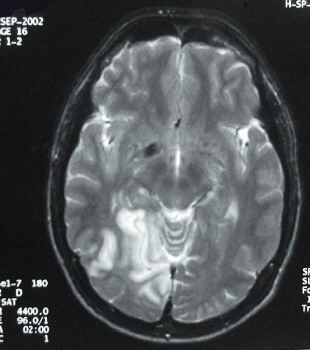

This patient presented with visual field loss and a brain scan is as shown above. a. What is this scan? b. What is the diagnosis? c. What is the visual field defect?

Answer aT-2 weighted MRI scan. Answer bRight occipital lobe infarction. Answer cLeft homonymous hemianopia.